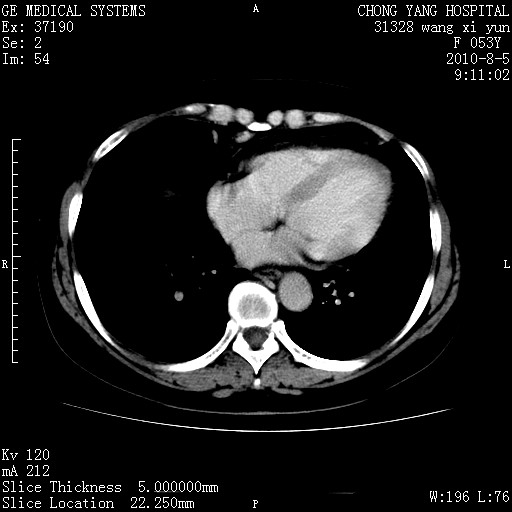

标题: CT28214:F41Y 血尿二十天,建议盆腔平扫加增强。

胆管细胞ca?

1)考虑肝左叶胆管细胞癌。2)脂肪肝。

支持胆管细胞ca。